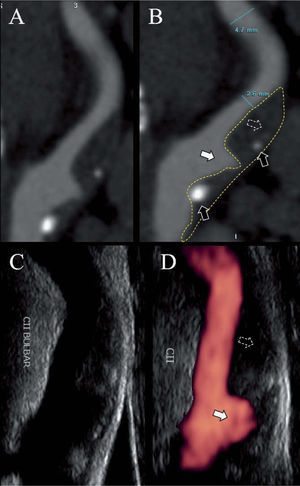

Espesor íntima-media, morfología, área y volumen de la placa carotídeaEn los últimos años se han logrado grandes avances en cuanto a la visualización e identificación de los componentes de la placa vulnerable mediante técnicas ultrasonográficas y la incorporación del doppler intravascular (IVUS, intravascular doppler ultrasound), A-RMN y A-TCM. La utilización de estos exámenes complementarios en la práctica diaria ya es corriente en varios centros especializados nacionales e internacionales (fig. 3). Otros métodos más sofisticados sólo se usan con fines de investigación: tomografía por emisión de positrones (PET), tomografía por emisión de fotón simple (SPECT) con acetazolamida, termografía extra o intravascular, tomografía de coherencia óptica (OCT) y elastografía, entre otros.

Ecodoppler con power-doppler y angiotomografía de arteria carótida interna. A y B: tomografía computarizada multicorte de la arteria carótida interna, que muestra una estenosis a nivel bulbar por una placa con componente fibrolipídico (flechas punteadas), escaso componente cálcico (flechas negras) y una gran úlcera (flechas blancas). C y D: la misma arteria evaluada por eco doppler (C) y power-doppler.

El espesor íntima-media (EIM) aumentado ha sido identificado como un predictor de infarto agudo de miocardio y stroke en la población general. Por cada 0,1mm de aumento en el EIM, el riesgo ajustado (por edad y sexo) de stroke aumenta un 18% (OR: 1,18; IC 95%: 1,16-1,21)49. El área de la placa es un mejor marcador de riesgo de stroke que el EIM, aunque puede resultar más difícil de cuantificar50. Ambos parámetros son considerados fenotipos ateroscleróticos con diferencias biológicas y genéticas50. A pesar del valor pronóstico de estos indicadores su uso en la práctica clínica no ha sido avalado todavía. Más recientemente se ha comenzado a utilizar un tercer marcador carotídeo de riesgo, el volumen de la placa cuantificado mediante doppler con reconstrucción tridimensional51.

Los signos de vulnerabilidad de la placa carotídea pueden ser visualizados con DVC, A-TCM y A-RMN. El método que ofrece mayor detalle es el IVUS.